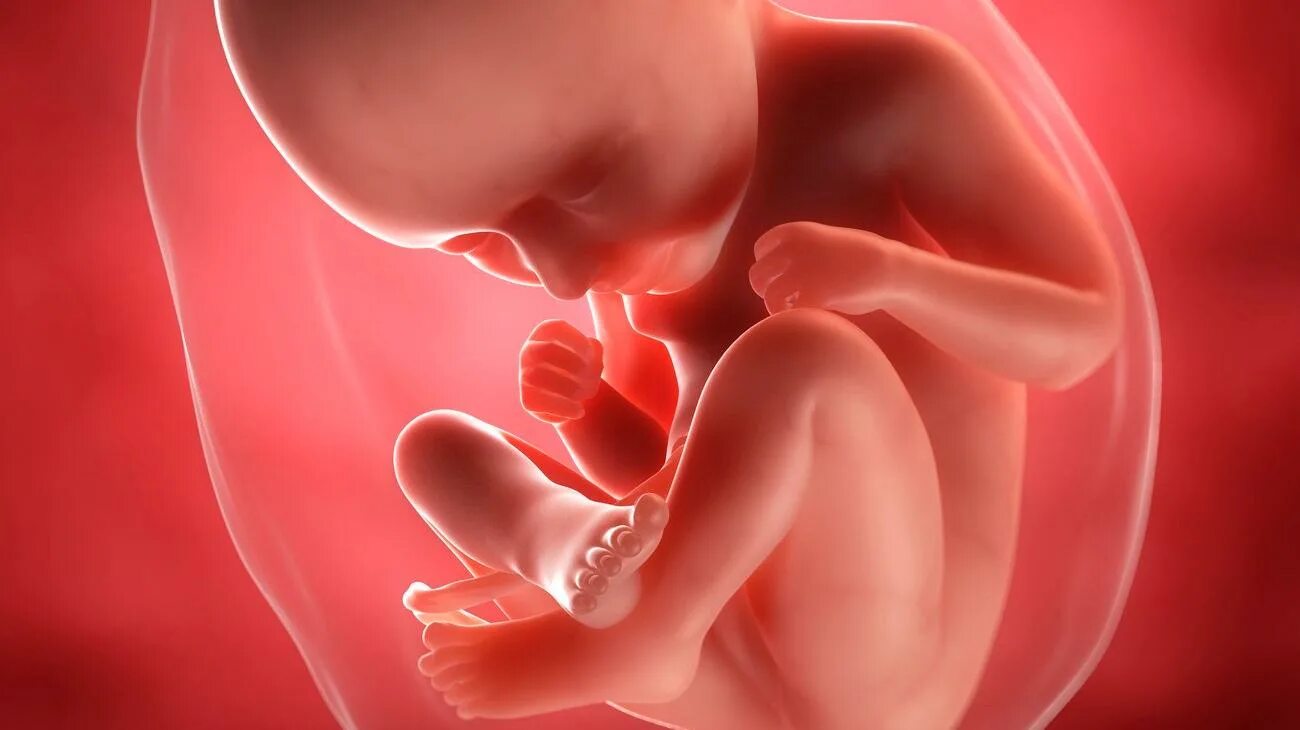

Ребенок в утробе 31 неделя